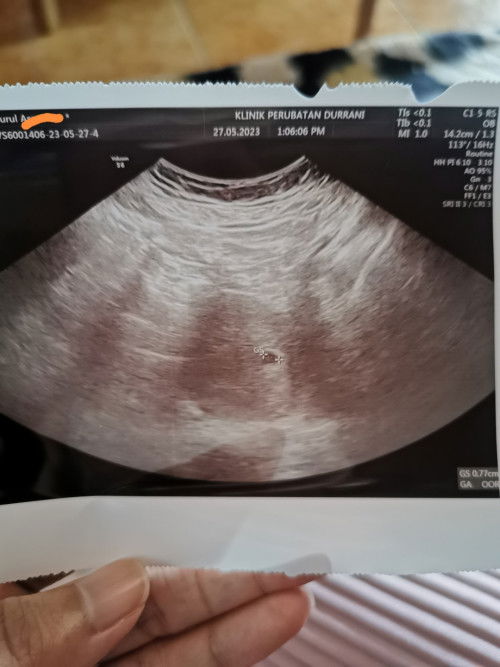

Tak tahu berapa weeks

Saya baru pergi scan td, tp doc xbley bagi details lagi brp weeks. Saya baru miscarriage last month n bulan ni terus positif upt. Saya dapat positf upt 2 minggu lps. Agak agak mommies saya brp weeks dah? #ingintahu #firstpregnancy